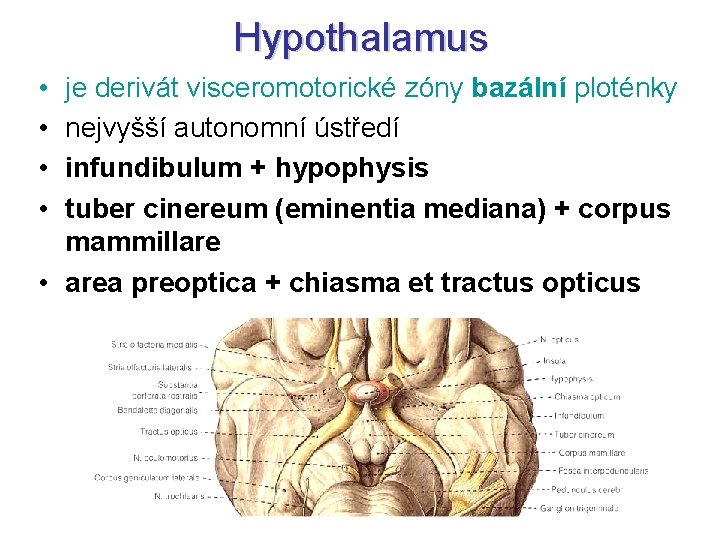

Hypothalamus • • je derivát visceromotorické zóny bazální ploténky nejvyšší autonomní ústředí infundibulum + hypophysis tuber cinereum (eminentia mediana) + corpus mammillare • area preoptica + chiasma et tractus opticus

Hypothalamus • infundibulum • tuber cinereum • corpora mammillaria • recessus infundibuli • recessus opticus

Hypothalamus – ohraničení • • nahoře: sulcus hypothalamicus dole: viditelný na dolní ploše mozku vpředu: lamina terminalis vzadu: přechází do tegmentum mesencephali • mediálně: 3. komora • laterálně: capsula interna